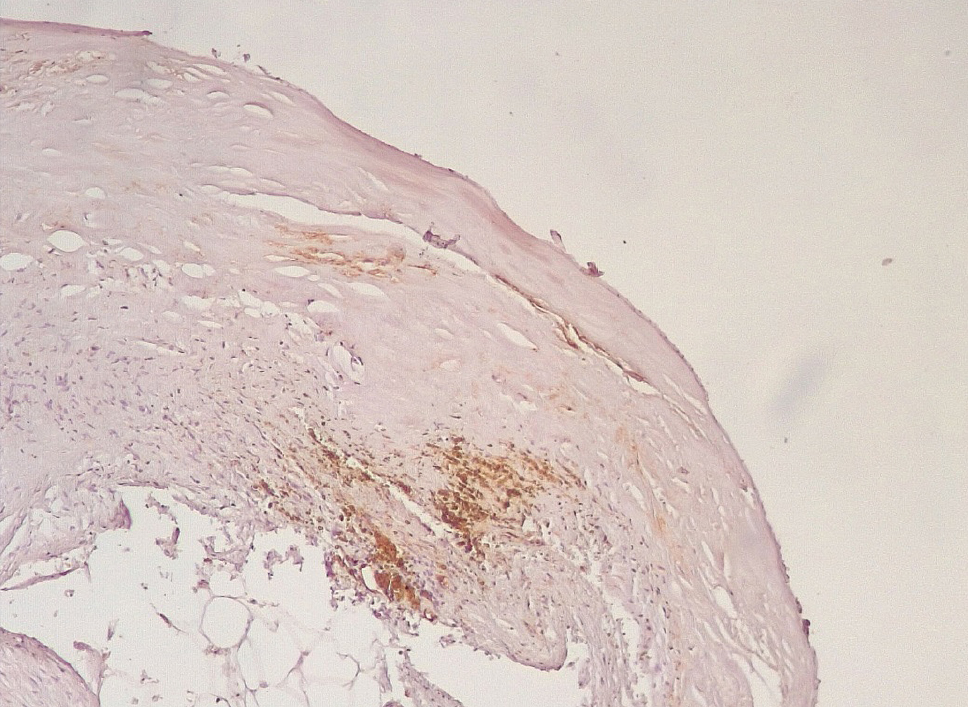

Маркер эндотелиальной дисфункции – фактор Виллебранда (ФВ) ярко экспрессировался в клетках эндотелия КА и субинтимально, что могло свидетельствовать о выраженной дисрегуляции коагуляционных свойств крови (рис. 5). В то же время экспрессия белка CD31 в указанные сроки после стентирования была слабовыраженной, что могло указывать на выраженные дистрофические изменения эндотелиальных клеток КА.

Рис. 5. Яркая экспрессия белка ФВ в клетках эндотелия, субинтимальных отделах КА (3–7-е сутки). Иммуногистохимическое исследование с антителами к vWF. Ув. ×200

Сохранялась резковыраженная яркая экспрессия ФВ как со стороны интимы, так и субинтимально, в участках альтерации атером (рис. 8). В то же время экспрессия белка CD31 была негативной на всем протяжении стенок КА.

Рис. 8. Яркая экспрессия ФВ в интиме и субинтимально в местах разрушения атером КА. Иммуногистохимическое исследование с антителами к vWF. Ув. ×200